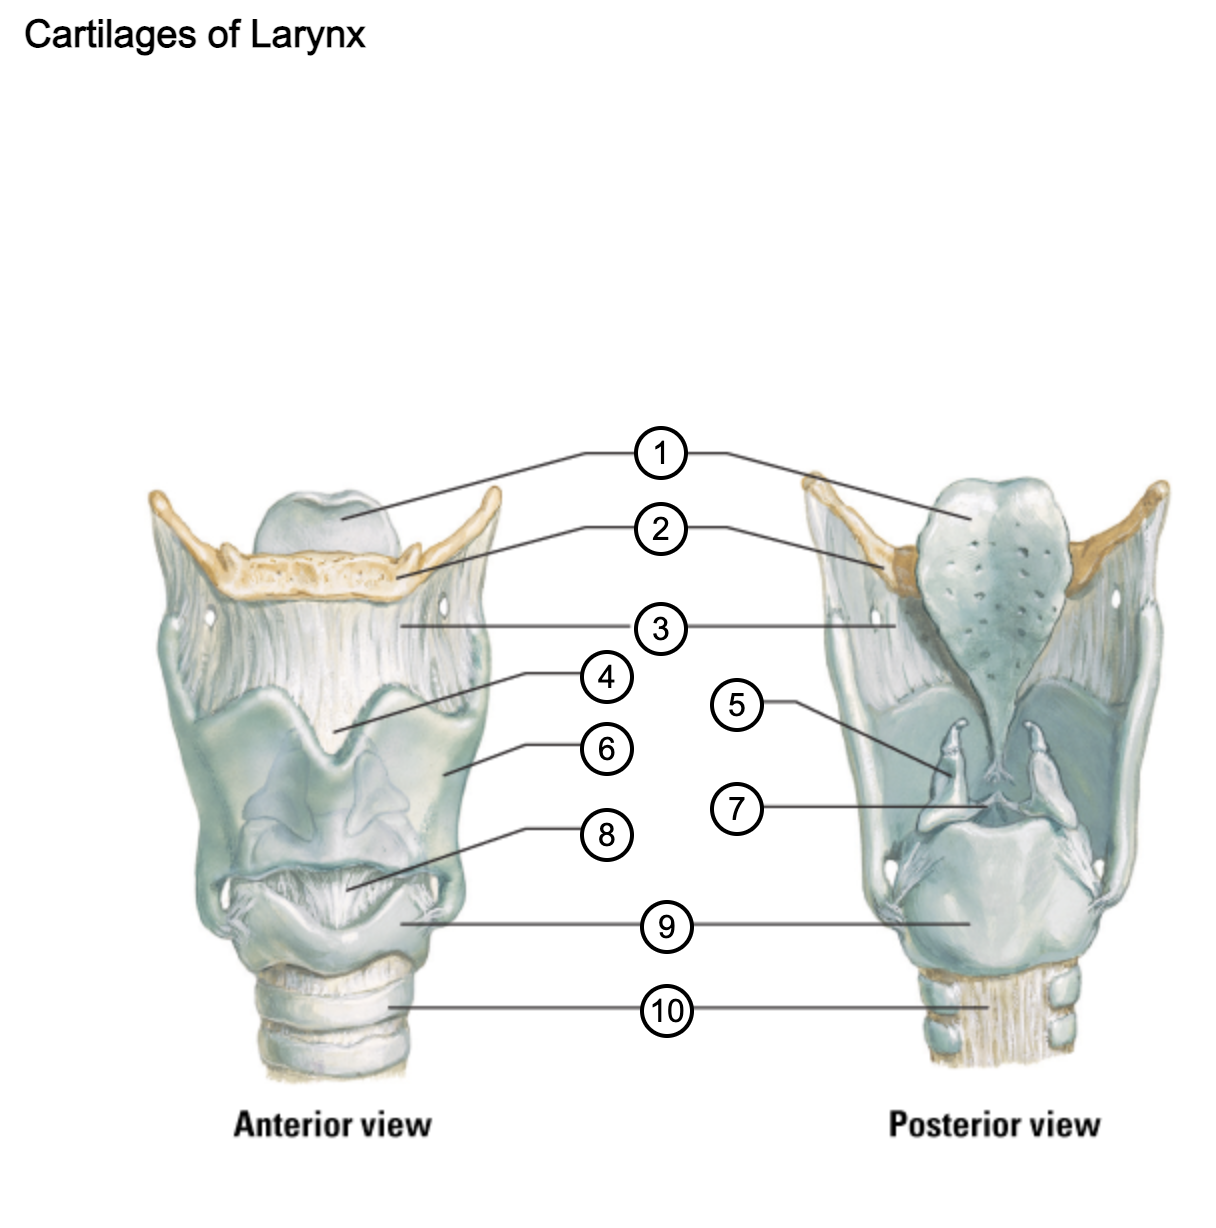

1

epiglottis

2

hyoid bone

3

thyrohyoid membrane

4

superior thyroid notch

5

arytenoid cartilage

6

lamina of thyroid cartilage

7

vocal ligament

8

median cricothyroid ligament

9

cricoid cartilage

10

trachea